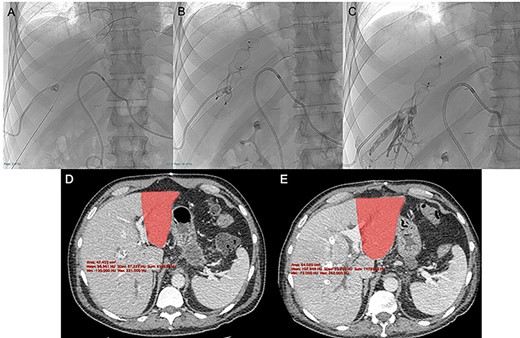

Contrast-enhanced computed tomography (CECT) and magnetic resonance cholangiography revealed a type IIIa Klatskin tumor, closely adherent to portal vein bifurcation and infiltrating the proximal left portal vein. The stenosis was hemodynamically significant at US-Doppler examination (Fig. 1A and B).

Since significant left portal vein narrowing at its origin due to tumor infiltration (A, B) contraindicated upfront right portal vein embolization, which was deemed potentially ineffective and at risk of favoring portal trunk thrombosis, porto-portal shunt by the mean of an autologous internal jugular vein graft interposition, followed by right and middle hepatic veins embolization, was performed (C, D).

Given the important narrowing of the proximal left portal vein, which would have jeopardized any attempt at inducing FLR hypertrophy, the patient first underwent surgical left portal vein recanalization. This was achieved by interrupting main and left portal vein outside the infiltrated area (which was deliberately not touched) and interposing an autologous internal jugular vein graft; portal bifurcation was by-passed, and portal flow was completely diverted to the left hemi-liver (Fig. 1C).

Unfortunately, CECT performed 3 weeks after the operation showed no increase in FLR volume, with partial reperfusion of multiple small intrahepatic right portal branches, characterized by reversed flow. Considering the technical difficulty of portal vein embolization (PVE) in this setting, percutaneous embolization of the right and middle hepatic veins (HVE) was considered as a salvage strategy (Fig. 1D).

Under local anesthesia and conscious sedation, the right and middle hepatic veins (HVs) were accessed under ultrasonographic guidance with 21G Chiba needles, 0.018″ guidewires and micropuncture sets (Meditalia Biomedica, Medolla, Italy) (Fig. 2A).

After US-guided percutaneous transhepatic access with micropuncture sets (A) the right and middle HVE was performed using two 90% oversized vascular plugs (B) and then completed with 2:1 Lipiodol-glue mixture (C), resulting in a 26.8% increase in volume of the FLR (501 vs. 395 cc) after 9 days with a kinetic growth rate (KGR) of 11.8 cc/days (D, E).

Two 0.035″ guidewires (Amplatz Super Stiff, Boston Scientific, Marlborough, MA) were advanced to the atrio-caval junction and, after accommodation of two 8F × 24 cm sheaths (Radifocus Introducer II, Terumo, Japan), 6 and 7 mmHg of endoluminal pressure were measured, respectively, in the right and middle HVs. After that, both HV were occluded with Amplatzer Vascular Plugs II (St-Jude Medical, Plymouth, MN), respectively, 22 and 16 mm in diameter (90% oversized), with the distal part deployed 10–15 mm proximal to the junction with the inferior vena cava to enable further surgical ligation (Fig. 2B). The embolization of the HVs and potential collaterals was distally completed with a 2:1 mixture of Lipiodol Ultrafluid (Guerbet, Villepinte, France) and Glubran 2 (GEM Italy, Viareggio, Italy) (Fig. 2C).

The CECT scan performed 9 days after the HVE showed a 26.8% increase in volume of the FLR (501 vs. 395 cc), resulting in a kinetic growth rate (KGR) of 11.8 cc/day. FRL/TLV ratio was 20.4% (+5.5%) and the FRL/sTLV ratio was 25.1% (+ 5.3%) (Fig. 2D and E).